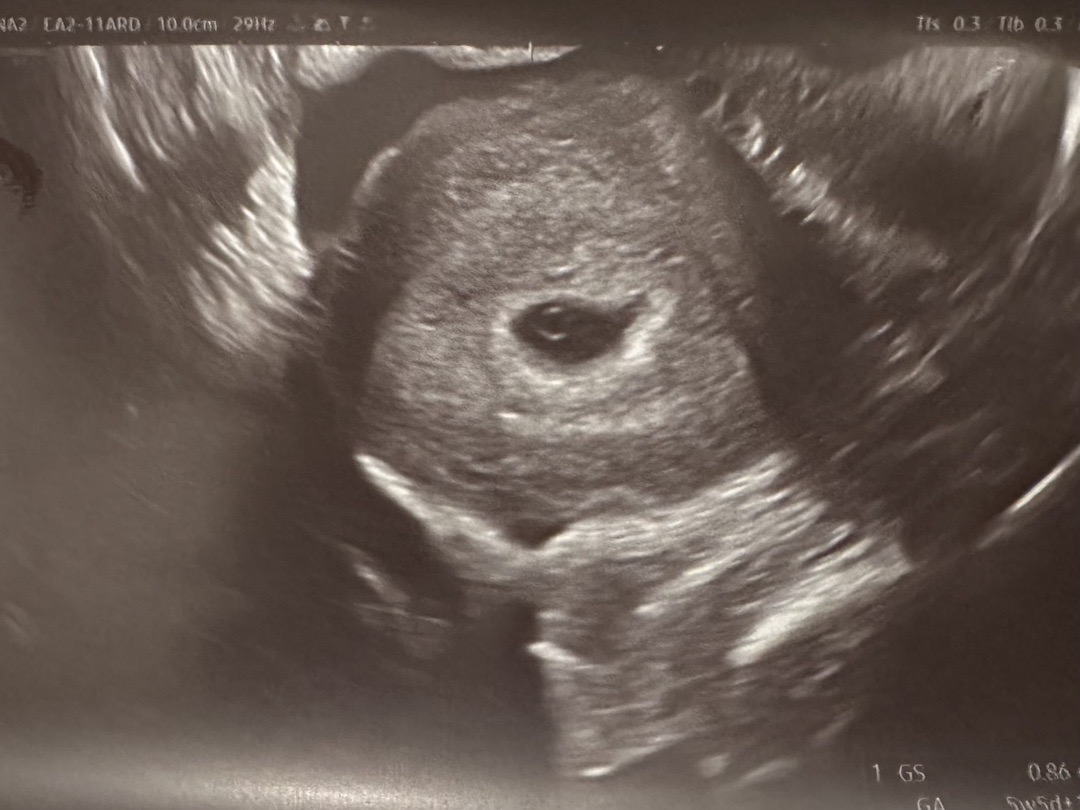

난황 보고왔어요! (5주 5일차)

5주 5일차입니다..! 다음주에 오라고 하셨는데 오늘 가서 초음파 봤더니 난황이 생겼어요🥹 동그란 반지같아요 ㅎㅎ 난황옆에 아기같이 보이는것도 있는거같다고 하셨는데 다음주에 심소 확인해보자고하고 기쁜 마음으로 나왔습니다 초음파 중간에 볼까말까 고민했었는데 보길 잘한거같아요🙏🏻